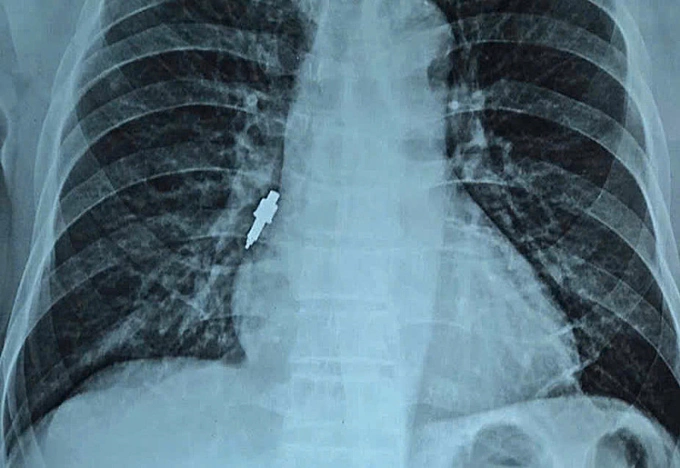

Dị vật kim loại nằm sâu trong đường thở. Ảnh: Bệnh viện cung cấp

Ngày 26/11,đại diện viện cho biết nội soi gắp thành công dị vật nằm sâu trong phế quản phải của bệnh nhân. Dị vật là một dụng cụ nha khoa bằng inox,trơn nhẵn,dài 2,5 cm và có đường kính lớn nhất lên tới 1 cm.

Kíp nội soi đánh giá đây là ca khó do dị vật kích thước lớn,bề mặt trơn trượt và nằm kẹt sâu. Các bác sĩ phải thao tác thận trọng để tránh làm rách phế quản,gây chảy máu hoặc đẩy dị vật xuống sâu hơn. Sau khi lấy được dụng cụ ra ngoài,bác sĩ tiếp tục bơm rửa sạch mủ và cặn máu ứ đọng. Hiện sức khỏe bệnh nhân đã ổn định.